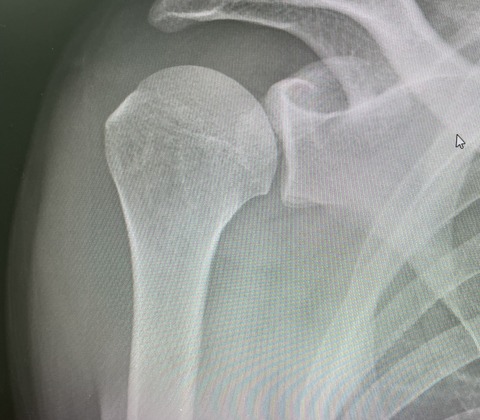

本日も、朝から夜まで、一般患者様を

見さしてもらいながら

トップアスリートが4人来ました

茨城トヨペット社会人野球、151キロを投げる

プロからスカウトをもらってる、ピッチャー、

IMG_8592

硬式社会人野球 147のキロを投げる、

元甲子園全国制覇をした、履正社高校の

エースピッチャー

IMG_8602

全日本高校空手道選手権優勝の  女子空手選手

IMG_8603

全日本モトクロス選手権、5回連続全日本

チャンピオンの

選手たちも来院されました!

IMG_8595

かなりハードでしたが、やりがいのある1日でした!